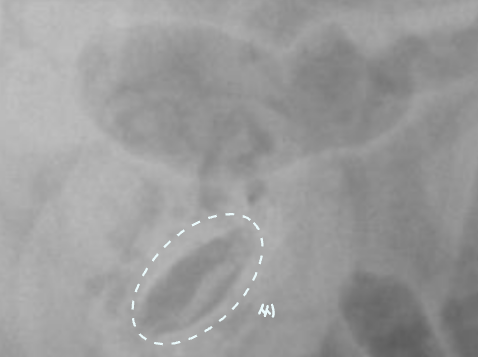

Intestinal Foreign body

| Stacking sign |

|---|

| ์ฅ์ด ์ปค์ ธ์ ์ข์ ๊ณต๊ฐ ์์ ์ฐจ๊ณก์ฐจ๊ณก ์์ด๋ฉฐ ๋ณด์ด๋ sign. |

| String sign / Accordian sign (์ ์ ์ด๋ฌผ) |

| ์ ์ ์ด๋ฌผ์ ์ํด ์ฅ(์ฃผ๋ฆ)์ด ๊ณ์ ๋ฐ๋ ค์ ๋ํ๋๋ sign. |

![]() ![]() ์ ์ ์ด๋ฌผ์ ์ฅ์ ์์ ํ ๋ง์ง ๋ชปํด fluid๊ฐ ์ ๋ฅ๋ ์ ์์. |